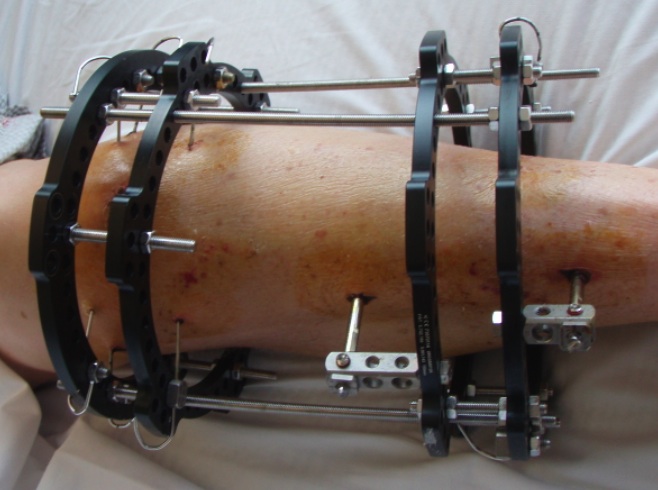

Deformity correction

Poor soft tissues

- prohibit ORIF

Non union

Infected non uniion

Malunion / deformity

Bone loss / bone transport / LLD